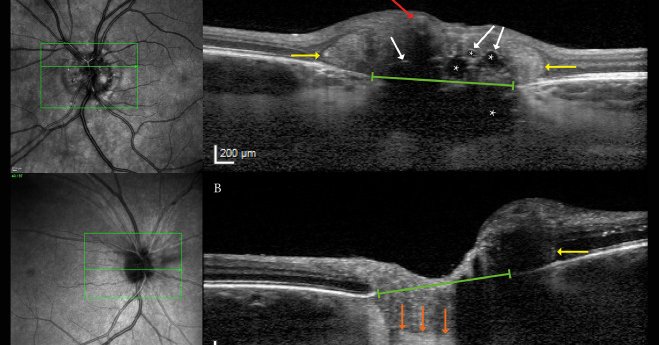

ODD-AION is an important form of visual loss, caused by #opticdiscdrusen. In this study in @AJOphthalmology, members of @CphOpticNerve Research Center investigate the fundamental underlying anatomic and vascular risk factors. Thanks to @VELUXFONDEN https://t.co/UYHjwPOfUK

Optic disc drusen (ODD) is an anatomical risk factor for nonarteritic anterior ischemic optic neuropathy (NA-AION). This study aimed to investigate the anatomical and vascular risk factors of...

Steffen Hamann & colleagues demonstrate that patients with optic disc drusen-associated NAION are younger, have fewer vascular risk factors, and smaller Bruch’s membrane openings than non-ODD-associated NAION. https://t.co/ImQjybsphH #neuro #eye #NeuroOphthalmology